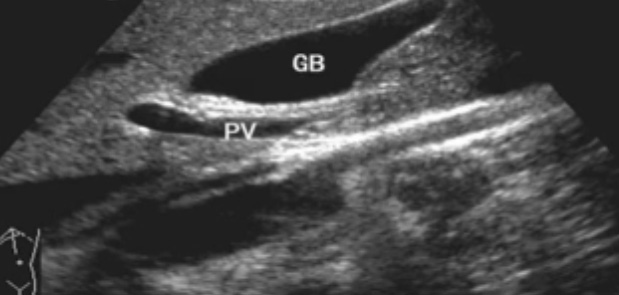

一、正常胆囊超声图像

胆囊的位置、形态、大小、壁厚,内部及附壁是否有异?;厣?尤其胆囊要注意颈部,还要看有没慢性炎症的征象,肿瘤或隆起样病变.正常胆囊声像图是像个瓣,胆囊正常大小,颈部指向肝门胆囊轮廓清晰,壁薄很光滑呈线状,囊内无回声,后壁回声增强。为什么无回声呢?因为胆汁是液体,水,血液这些都是无回声的。胆囊颈和门静脉或门脉右支根部之间有一线状高回声带连结,这是识别胆囊位置的重要标志。胆囊长径一般不超90mm;前后径2030mm,不超过40m正常充盈胆囊壁厚<3mm。 胆囊皱褶非常常见,

肝内胆管-无胆管扩张的情况下,超声一般只能显示胆管的一、二级支,不能显示二级以上的肝内胆管肝外胆管(声像图上大致分为两段)上段与门静脉伴行,位于门静脉主干的右前方;下段与下腔静脉伴行并延伸进入胰头背外侧。胆道、肝动脉与门静脉的关系。